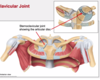

The left and right sternoclavicular joints

What type of joints are sternoclavicular joints?

True joints

Which joints connect the upper limb to the trunk and what type of joint is each one?

Left and right sterno-clavicular joints → True joints